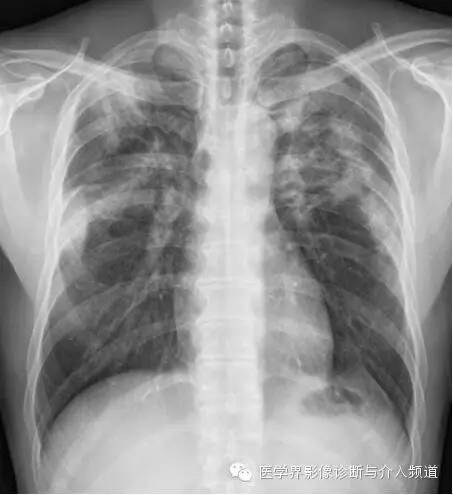

初始胸片

初始胸片示两肺野多灶性斑片影,其中两肺上野靠近外周可见边界欠清的实变影,这是典型的慢性嗜酸性粒细胞性肺炎“肺水肿反转影”的表现。CT示两肺叶多灶性非节段性实变影,病变以两上肺周围性分布为主。

CEP的典型影像学表现:普通X线平片为非节段性、分布广泛互相融合的肺泡及间质性实变,病变以中上肺周围性分布为主,表现为“肺水肿反转影”。CT或HRCT表现为一侧或两侧融合性实变、斑片状实变、磨玻璃影、条带状致密影,实变灶与正常肺组织的分界截然清楚。此种典型征象并非见于所有CEP病例。